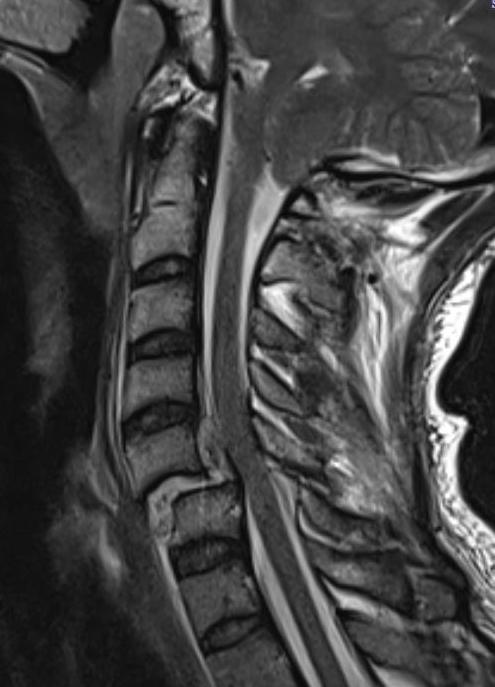

MRI

Look for herniated disc

- ? large disc could worsen neurology with skull traction / closed reduction

- ? indication for anterior approach / discetomy / fusion

Herniated disc on MRI seen after facet joint dislocation